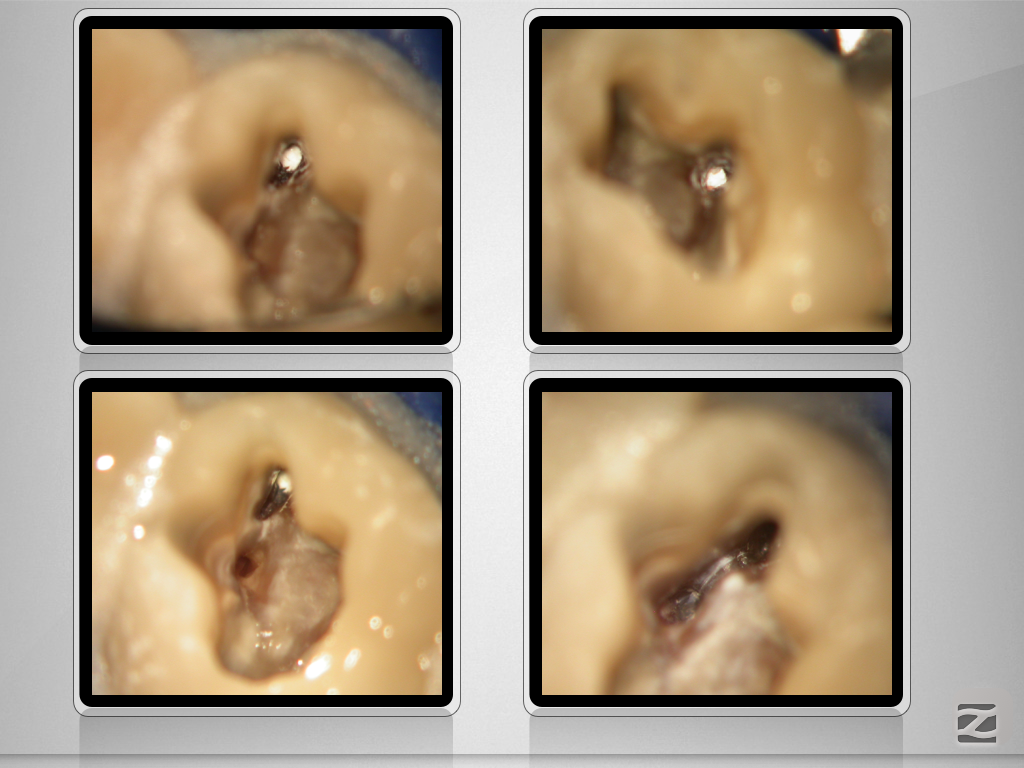

16d-009

Revision nach Resektion